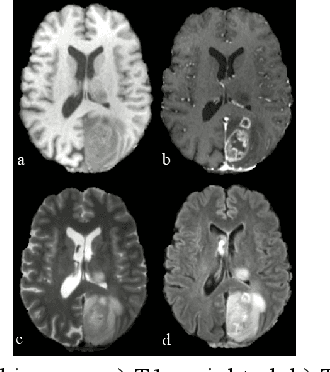

Abstract:Accurate brain tumor typing requires integrating heterogeneous clinical evidence, including magnetic resonance imaging (MRI), histopathology, and pathology reports, which are often incomplete at the time of diagnosis. We introduce CoRe-BT, a cross-modal radiology-pathology-text benchmark for brain tumor typing, designed to study robust multimodal learning under missing modality conditions. The dataset comprises 310 patients with multi-sequence brain MRI (T1, T1c, T2, FLAIR), including 95 cases with paired H&E-stained whole-slide pathology images and pathology reports. All cases are annotated with tumor type and grade, and MRI volumes include expert-annotated tumor masks, enabling both region-aware modeling and auxiliary learning tasks. Tumors are categorized into six clinically relevant classes capturing the heterogeneity of common and rare glioma subtypes. We evaluate tumor typing under variable modality availability by comparing MRI-only models with multimodal approaches that incorporate pathology information when present. Baseline experiments demonstrate the feasibility of multimodal fusion and highlight complementary modality contributions across clinically relevant typing tasks. CoRe-BT provides a grounded testbed for advancing multimodal glioma typing and representation learning in realistic scenarios with incomplete clinical data.

Abstract:Segmentation is the identification of anatomical regions of interest, such as organs, tissue, and lesions, serving as a fundamental task in computer-aided diagnosis in medical imaging. Although deep learning models have achieved remarkable performance in medical image segmentation, the need for explainability remains critical for ensuring their acceptance and integration in clinical practice, despite the growing research attention in this area. Our approach explored the use of contrast-level Shapley values, a systematic perturbation of model inputs to assess feature importance. While other studies have investigated gradient-based techniques through identifying influential regions in imaging inputs, Shapley values offer a broader, clinically aligned approach, explaining how model performance is fairly attributed to certain imaging contrasts over others. Using the BraTS 2024 dataset, we generated rankings for Shapley values for four MRI contrasts across four model architectures. Two metrics were proposed from the Shapley ranking: agreement between model and ``clinician" imaging ranking, and uncertainty quantified through Shapley ranking variance across cross-validation folds. Higher-performing cases (Dice \textgreater0.6) showed significantly greater agreement with clinical rankings. Increased Shapley ranking variance correlated with decreased performance (U-Net: $r=-0.581$). These metrics provide clinically interpretable proxies for model reliability, helping clinicians better understand state-of-the-art segmentation models.

Abstract:Deep learning has been successfully applied to medical image segmentation, enabling accurate identification of regions of interest such as organs and lesions. This approach works effectively across diverse datasets, including those with single-image contrast, multi-contrast, and multimodal imaging data. To improve human understanding of these black-box models, there is a growing need for Explainable AI (XAI) techniques for model transparency and accountability. Previous research has primarily focused on post hoc pixel-level explanations, using methods gradient-based and perturbation-based apporaches. These methods rely on gradients or perturbations to explain model predictions. However, these pixel-level explanations often struggle with the complexity inherent in multi-contrast magnetic resonance imaging (MRI) segmentation tasks, and the sparsely distributed explanations have limited clinical relevance. In this study, we propose using contrast-level Shapley values to explain state-of-the-art models trained on standard metrics used in brain tumor segmentation. Our results demonstrate that Shapley analysis provides valuable insights into different models' behavior used for tumor segmentation. We demonstrated a bias for U-Net towards over-weighing T1-contrast and FLAIR, while Swin-UNETR provided a cross-contrast understanding with balanced Shapley distribution.

Abstract:The integration of machine learning in magnetic resonance imaging (MRI), specifically in neuroimaging, is proving to be incredibly effective, leading to better diagnostic accuracy, accelerated image analysis, and data-driven insights, which can potentially transform patient care. Deep learning models utilize multiple layers of processing to capture intricate details of complex data, which can then be used on a variety of tasks, including brain tumor classification, segmentation, image synthesis, and registration. Previous research demonstrates high accuracy in tumor segmentation using various model architectures, including nn-UNet and Swin-UNet. U-Mamba, which uses state space modeling, also achieves high accuracy in medical image segmentation. To leverage these models, we propose a deep learning framework that ensembles these state-of-the-art architectures to achieve accurate segmentation and produce finely synthesized images.

Abstract:Tumor segmentation from multi-modal brain MRI images is a challenging task due to the limited samples, high variance in shapes and uneven distribution of tumor morphology. The performance of automated medical image segmentation has been significant improvement by the recent advances in deep learning. However, the model predictions have not yet reached the desired level for clinical use in terms of accuracy and generalizability. In order to address the distinct problems presented in Challenges 1, 2, and 3 of BraTS 2023, we have constructed an optimization framework based on a 3D U-Net model for brain tumor segmentation. This framework incorporates a range of techniques, including various pre-processing and post-processing techniques, and transfer learning. On the validation datasets, this multi-modality brain tumor segmentation framework achieves an average lesion-wise Dice score of 0.79, 0.72, 0.74 on Challenges 1, 2, 3 respectively.